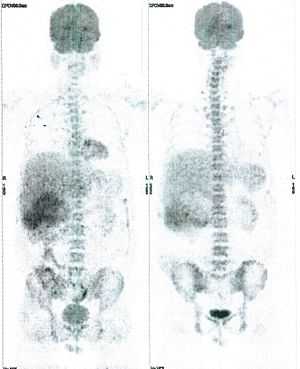

CASE NO: 4 (PROSTATE CANCER)

A middle-aged man with castration resistant prostate cancer and massive bone metastases, failed all currently available cancer treatment, including with the new and expensive drug XTANDI. After a few treatment, most of the bone metastases went into remission, and the remaining ones are less active. Treatment will continue. Cases no: 3 and 4 show that terminal prostate cancer today can be cured with our new cancer treatment.